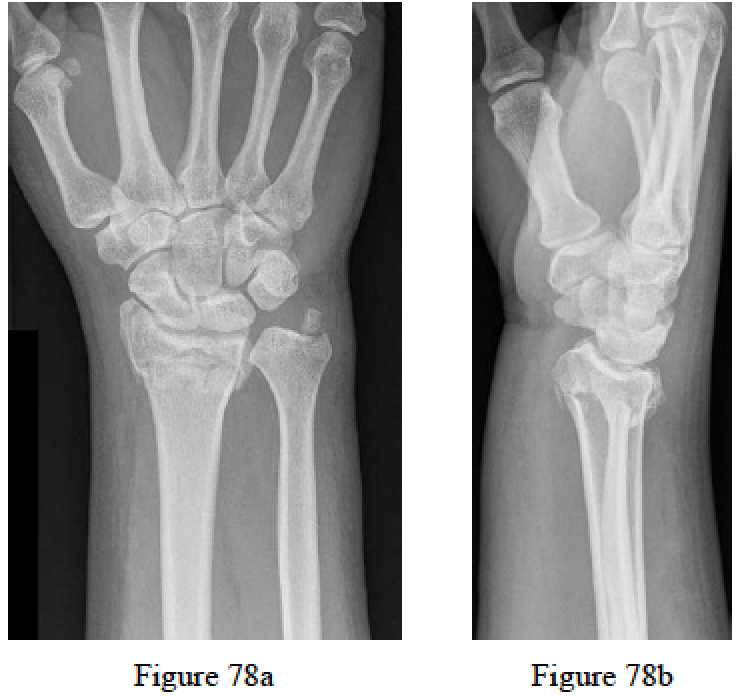

Kim JK, Yun YH, Kim DJ, Yun GU. Comparison of united and nonunited fractures of the ulnar styloid following volar-plate fixation of distal radius fractures. Injury. 2011 Apr;42(4):371-5. Epub 2010 Oct 20.PubMed PMID: 20961540.

Sammer DM, Shah HM, Shauver MJ, Chung KC. The effect of ulnar styloid fractures on patient-rated outcomes after volar locking plating of distal radius fractures. J Hand Surg Am. 2009 Nov;34(9):1595- 602. PubMed PMID: 19896004.